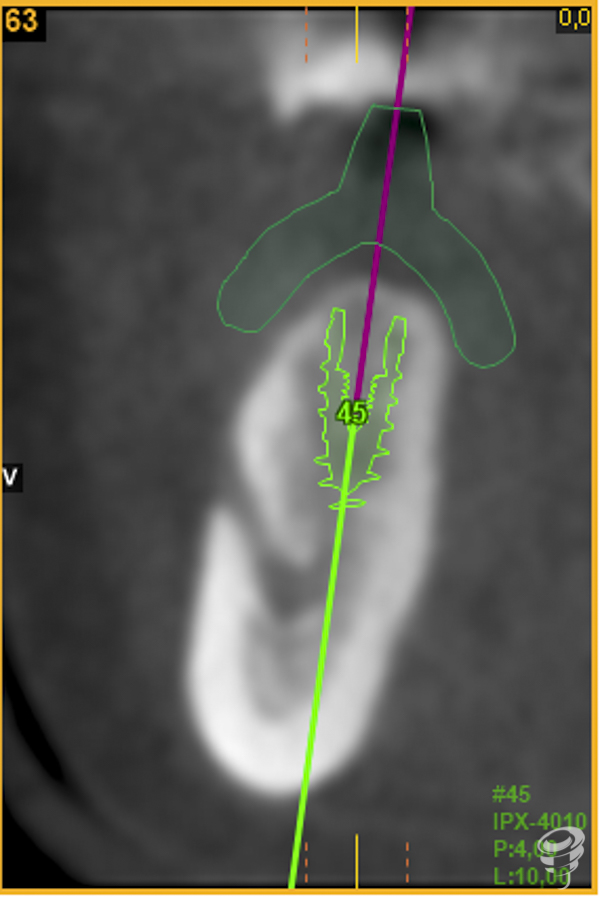

A.M.R Paciente de 40 años de edad, de sexo femenino, edéntula parcial, no fumadora y sin antecedentes médicos de interés. La paciente fue evaluada radiológicamente con una tomografía computarizada de haz cónico y se procedió a la planificación de su caso mediante el sistema informático Galimplant 3D Exacto®. Se planificaron dos implantes galimplant de 4X10mm (IPX 4010).

Una vez realizada la planificación de los dos implantes, se lleva a cabo la impresión de la férula quirúrgica dento-soportada con dos orificios cilíndricos adaptados a la fresa pin de 2 milímetros de diámetro. Esta fresa tiene la función de guiar tridimensionalmente la posición del implante.

A posteriori, se retira la guía quirúrgica y se realiza el fresado con la fresa Stop de 2 mm de diámetro y 14 mm de longitud directamente sobre los lechos implantarios. Esta fresa creará el lecho implantario idóneo (2 mm infra óseo) ya que el espesor mucoso en este caso es de 2mm.